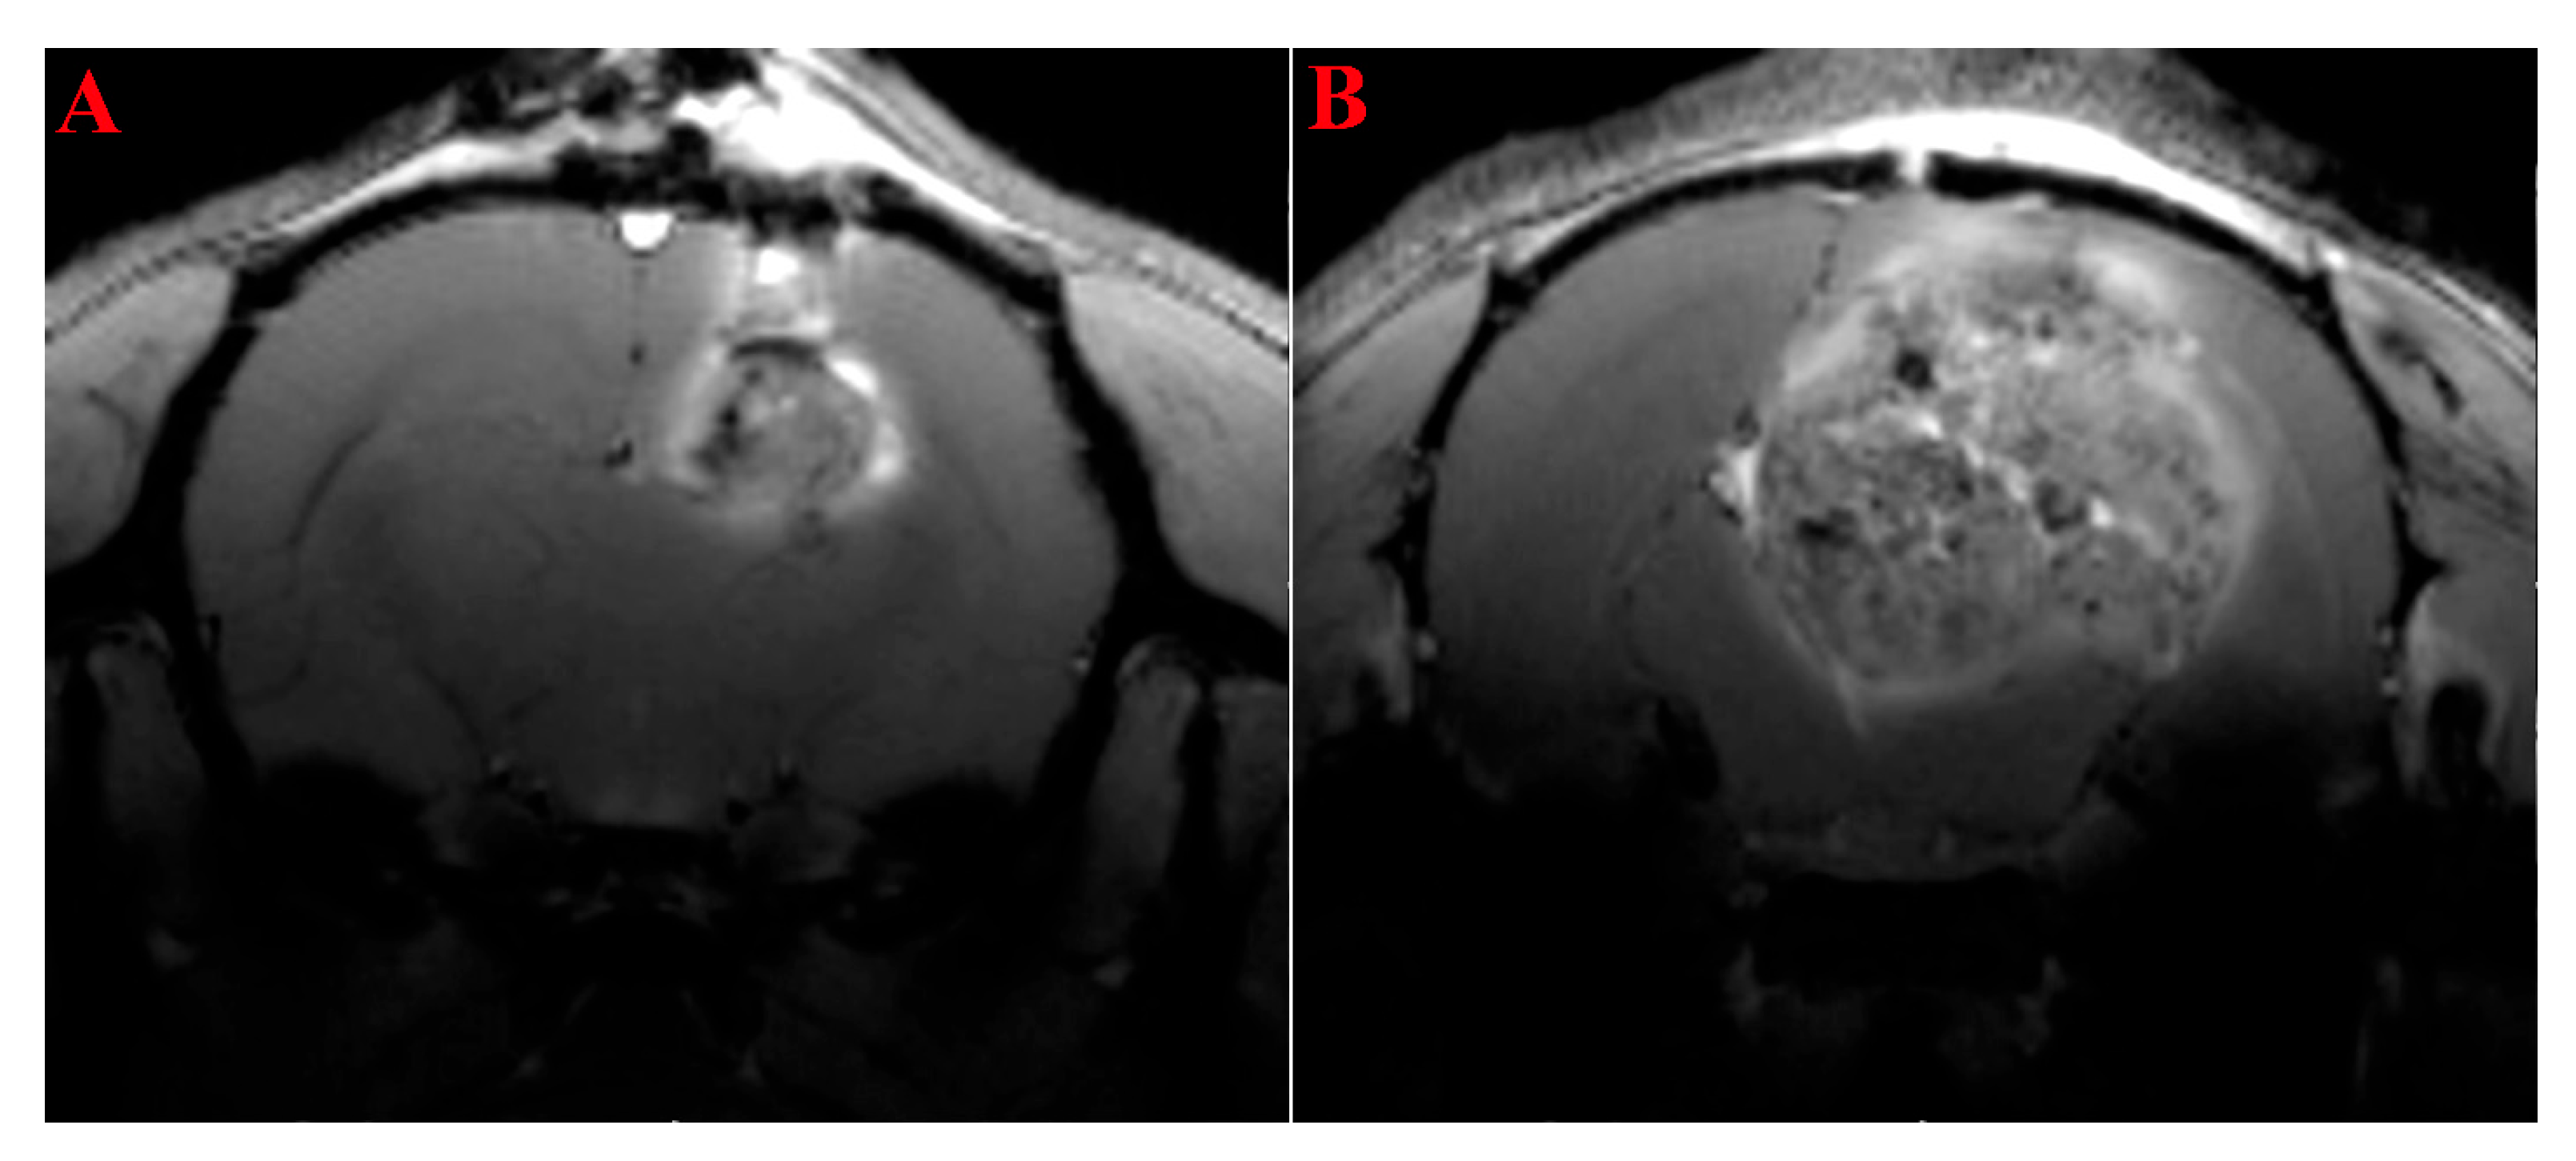

2.1. MRI Study of the Rats’ Brain with Transplanted Glioma 101.8